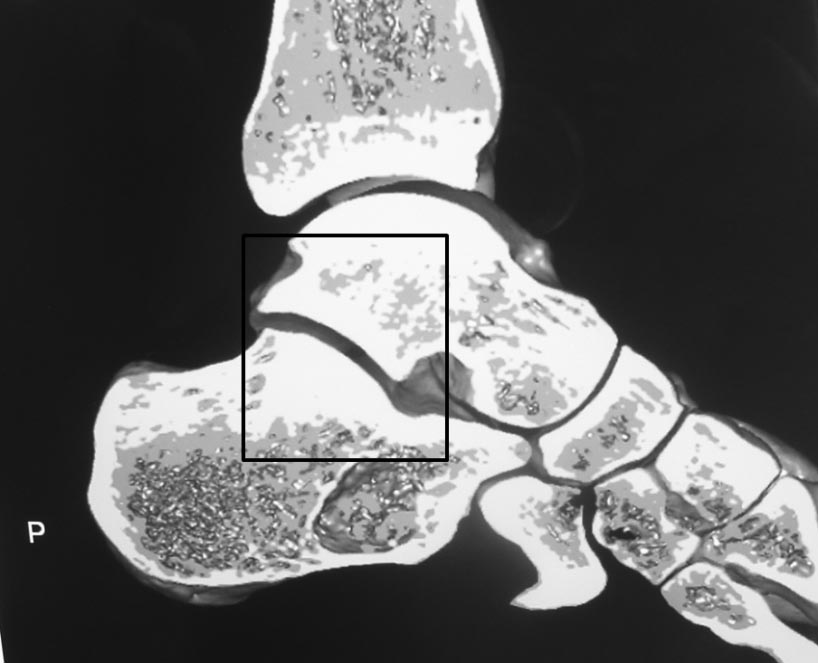

Во вложении всего два примера нормальных взаимоотношений в подтаранном суставе. Постарался подобрать похожие на Вашу проекции. На всех снимках выделена область, где суставные поверхности таранной и пяточной костей всегда должны быть параллельны. В Вашем случае эти линии пересекаются. Подвывих очевиден.